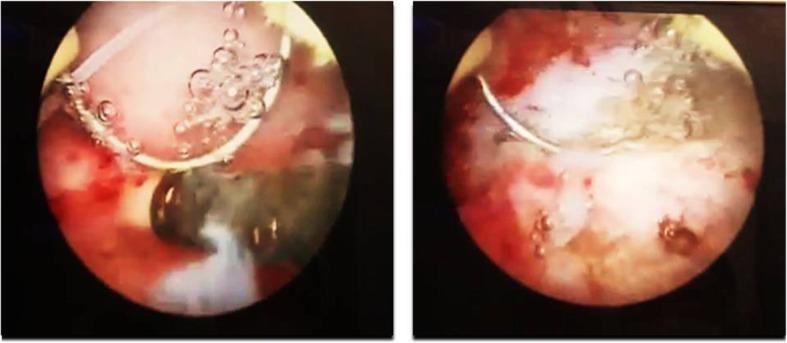

In this study, a case of copper IUD migration through cesarean scar defect is presented, in such a way that was successfully managed by cystoscopic removal. A 31-year-old female with a history of lower urinary symptoms referred to the clinic for her secondary infertility work-up. A copper IUD outside the uterus in the bladder was found using hysterosalpingraphy. A plain abdominal radiography also confirmed the presence of a T-shaped IUD in the pelvis. According to ultrasound, the copper IUD was partly in the bladder lumen and within the bladder wall. The patient had a history of an intrauterine device insertion eight years ago followingher second cesarean delivery. Three years later, her IUD was expelled, and another copper IUD was inserted. Thesecond copper IUD was alsoremoved while she decided to be pregnant. The patient finally underwent a hysteroscopic cystoscopy. The intrauterine device with its short arms embedded in the bladder wall was successfully extracted through the urethra.